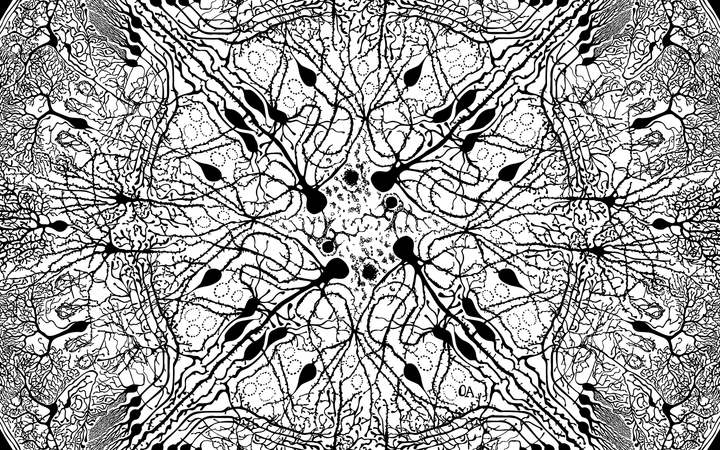

Väitöstutkimuksen ohessa Alitalo on myös tuonut esiin tiedettä, psykiatrisia sairauksia ja yhteiskunnallisia epäkohtia esiin taiteen kautta. Viime vuosina teoksia on ollut esillä muun muassa Farmasian tiedekunnan järjestämässä Art Meets Science -näyttelyssä, Keravalla 2024 järjestetyssä Purkutaide-näyttelyssä, sekä Psykedeelit ja luovuus kotimaisessa kuvataiteessa -kirjassa ja sen julkaisun yhteydessä järjestetyssä näyttelyssä. Hän on mukana myös 17.6.2025 avattavassa “Parempi Maailma” -Purkutaidenäyttelyssä Arabia135-korttelissa Helsingissä. Omaleimaisesta geometrisesta ja pikkutarkasta tyylistään Alitalo palkittiin ensimmäisessä Perttu Häkkisen säätiön järjestämässä gaalassa 2019.

Synaptogenesis -taideteoksen taustaa Okon kertomana

"Kun sain työpisteeni yliopistolta, löysin kasan 50 vuotta vanhoja mikroskooppilaseja, jotka olivat yhä kuin uutta vastaavassa kunnossa. Näytteiden tapaan, Synaptogenesis-mandalan tummat hermosolut ovat suljettu läpinäkyvään suojaan, joka leikkii sisällön optisilla ominaisuuksilla. Konseptuaalisesti mandala on meditaatio neurotieteen syntymällä ja kuolemalla, alan yhteydestä taiteeseen, sekä pyrkimyksilläni löytää oma paikkani tässä himmelissä.

Santiago Ramón y Cajal ’n (1852–1934) piirrosten innoittamat hermosolut ovat valittu masennuslääketutkimukseeni liittyviltä aivoalueilta. Ramón y Cajal toivoi ryhtyvänsä taiteilijaksi, mutta vanhempiensa painostamana valitsi lääketieteellisen uran. Tutkimuksessaan hän kuitenkin yhdisti taidetta ja tiedettä kuvaamalla keskushermoston mikroskooppista rakennetta. Luomiensa kuvien ansiosta hän ansaitsi Nobelin palkinnon 1906 ja tunnustuksen modernin aivotutkimuksen luojana.

Synaptogenesis on kunnianosoitus edesmenneelle Ronald S. Dumanille (1954–2020), jonka ansiosta ymmärrämme paljon enemmän ketamiinin solutason masennuslääkevaikutuksesta. Minulla oli suuri kunnia esitellä Ronille näyttelyni hänen vieraillessaan Suomessa hieman ennen kuolemaansa."